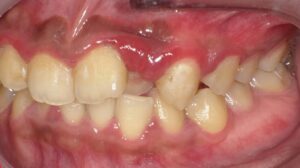

プラークコントロールが歯肉炎の改善と再発に及ぼす影響:初診・1か月後・3か月後の比較症例

⚠️初診時

プラーク付着による歯肉の腫脹・発赤が顕著

初診時は、上顎前歯部を中心に歯茎が赤く腫れ、ブラッシング時の出血も認められる状態でした。プラークの付着が多く、炎症が全体に広がっていることが確認できます。特に左上2番の舌側転位により清掃不良が生じ、歯茎の腫れが顕著です。